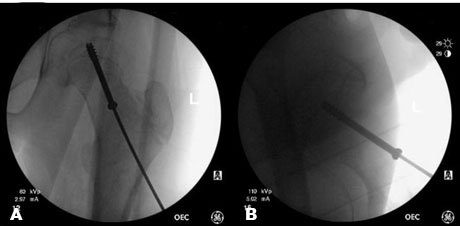

Radiographs at that time demonstrated cutout of the cannulated screw in the setting of a SCFE with further displacement (Figure 3A and Figure 3B). Physical exam was similar to his initial presentation.

He returned to the operating room on hospital day three of his second admission for conversion of the prior left hip surgery to an uncemented total hip arthroplasty (Figure 4A and Figure 4B). He tolerated the procedure well and there were no complications. His post-op course was uneventful, and he was discharged home and stable condition on post-op day two. He was made full weight bearing on the left lower extremity immediately after surgery without issues.

Figure 3: (A and B) Anterior-posterior (AP) pelvis and oblique view of the left hip demonstrating screw cutout and worsening of the previously repaired SCFE.

Figure 4: (A and B) Anterior-posterior (AP) and lateral hip radiographs demonstrating a total hip arthroplasty.